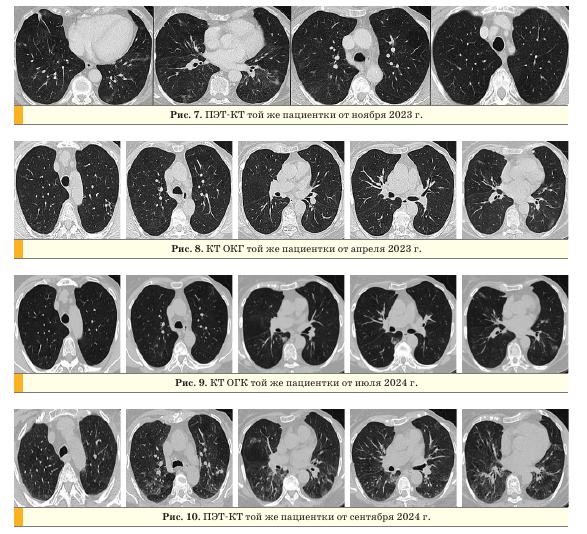

Проведен онкоконсилиум, определена тактика лечения. С июля 2022 г. по август 2023 г. пациентка находилась на схеме терапии палбо- циклиб + летрозол + золедроновая кислота, на фоне которой отмечалось исчезновение кашля и одышки. По данным позитронно-эмиссионной

томографии (ПЭТ) с КТ от ноября 2023 г. отмечалась значительная положительная динамика в виде регресса ранее выявляемых изменений в легких (рис. 7).

В апреле 2023 г. пациентка перенесла острое респираторное заболевание с явлениями брон- хиолита в I—II сегменте левого легкого, антибактериальную терапию не принимала. В апреле 2024 г. находилась на стационарном лечении в связи с новой коронавирусной инфекцией COVID-19. При контрольном обследовании на КТ ОГК и ПЭТ-КТ определялись признаки прогрессирования в виде роста очагов и появления новых очагов в легких и костях.

Динамика данных рентгенологических исследований представлена на рис. 8-10.